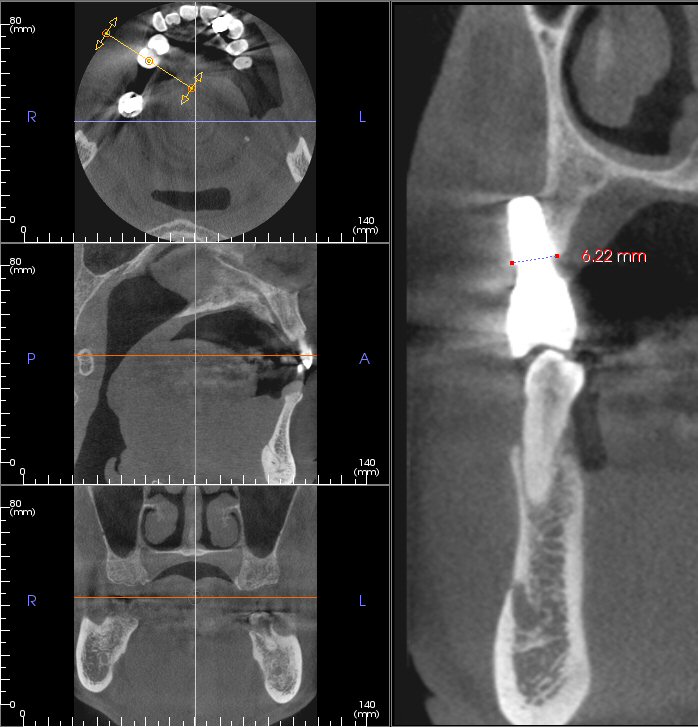

Another case of bad implant placement (which was done elsewhere) is shown in Fig. 3 (photo) and Fig. 4 (cross-sections of the CBCT scan). In this case, the implant is almost completely out of the bone. The site is of the upper right second premolar (Tooth #4). Even if the dentist had placed the implant in a perfect position and orientation, the bone width (in buccal-palatal direction) would still have been too small for this implant (6.22 mm, measured at the implant-platform level). According to the patient, the dentist who placed three (3) implants on him. But two (2) fell out, and only one remains. The dentist took some radiograph(s), presumably, PA or BW or both, and then told the patient, "The bone looks good."

Fig. 4. Implant for Tooth #4 site is outside of the bone (CBCT scan, with buccal-palatal cross-section)